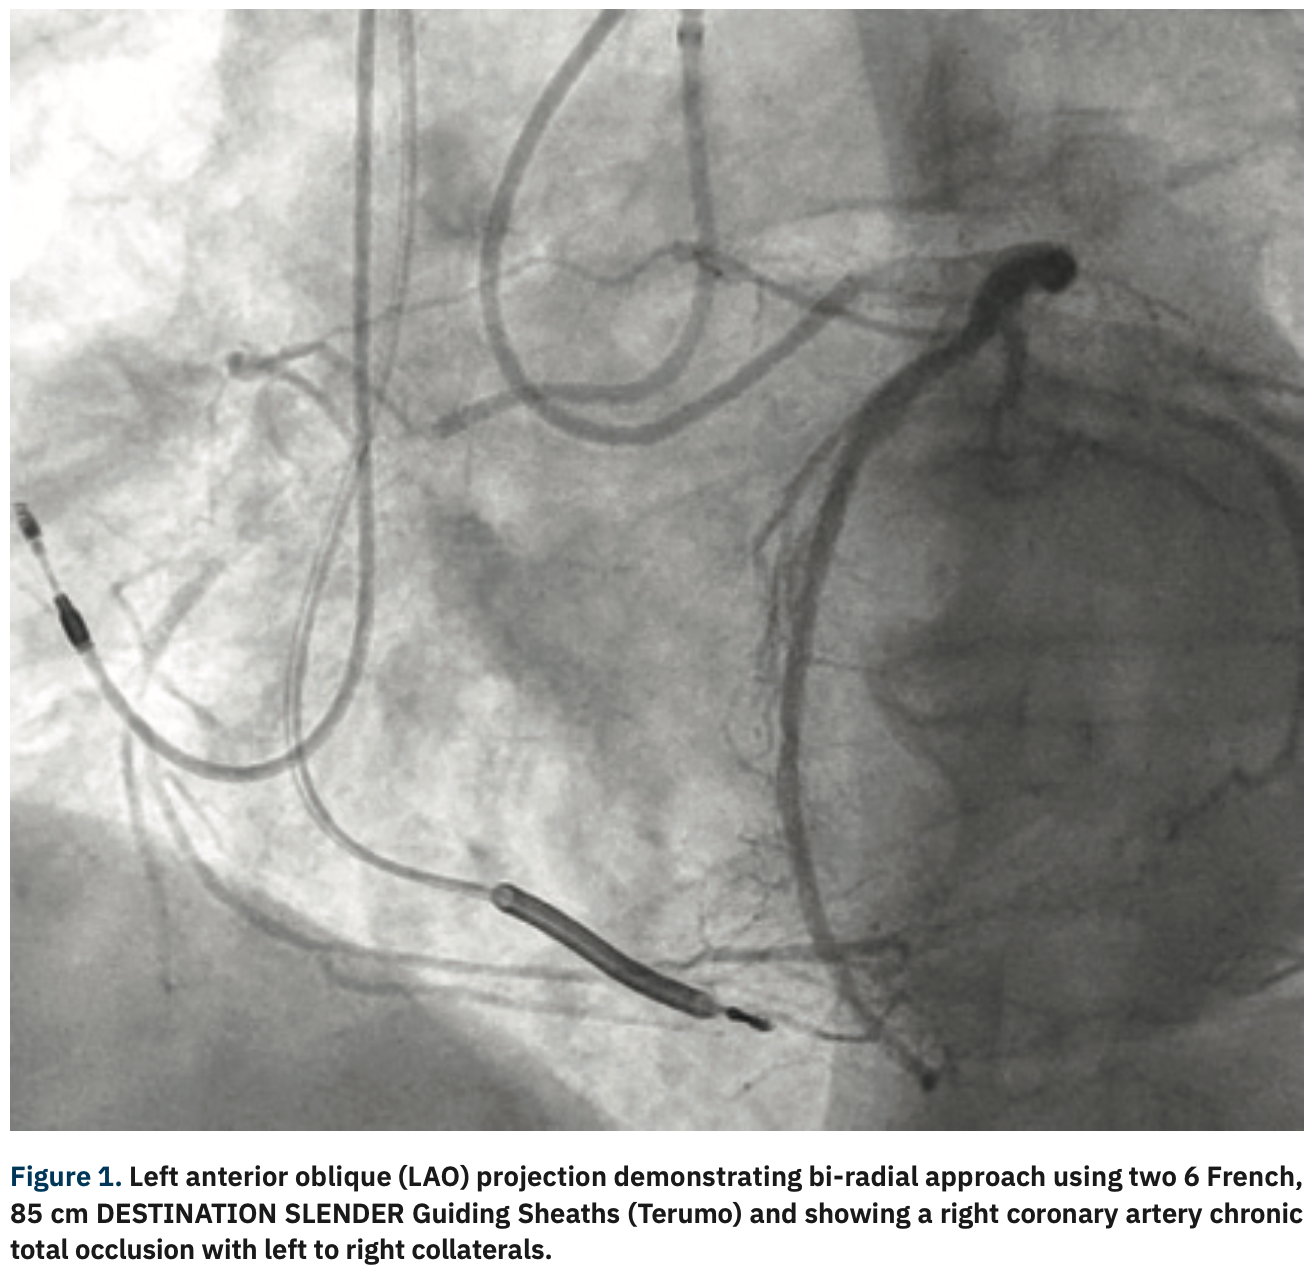

While the trend in percutaneous coronary intervention has been towards the use of smaller access and a radial artery approach, the technical challenges posed by chronic total occlusions have offered resistance to this transition for the bulk of operators. Most operators rely on dual femoral access with 8 French (Fr), 45 cm or longer sheaths that provide maximum support and straighten iliac artery tortuosity. There are, however, several disadvantages to the femoral approach, including peripheral artery disease that can increase the difficulty of access, absence of femoral access, increased minor and major bleeding risk, and inability to use closure devices, which can increase the length of patient hospital stay and cost of the overall procedure. Due to these disadvantages, operators may rely on a combination approach, using both femoral and radial access. A bi-radial access can also be used, but has been routinely criticized for insufficient support, frequently required to cross chronic calcified lesions, overcome tortuosity, and deliver devices. Fortunately, the introduction of the 75 and 85 cm R2P™ DESTINATION SLENDER™ Guiding Sheath (Terumo) offers the ability to attenuate subclavian tortuosity and maximize support at the tip of the guide. Here, we present a case of a right coronary artery chronic total occlusion treated via a bi-radial approach with two 85 cm R2P DESTINATION SLENDER Guiding Sheaths.

A 6 Fr, 10 cm GLIDESHEATH SLENDER® Introducer Sheath (Terumo) was used to gain access in the right radial and left distal radial arteries. Two hundred (200) mcg of intra-arterial nitroglycerin and 200 mcg of intra-arterial nicardipine were given for each access. Each access point was exchanged for a 6 Fr, 85 cm R2P DESTINATION SLENDER Guiding Sheath (Terumo) over a 180 cm, .035-inch J-tipped guidewire. A 6 Fr Amplatz Left (AL) 0.75 VISTA BRITE Guiding Catheter (Cordis) was used to engage the right coronary artery and a 6 French XB 3.5 ADROIT™ Guiding Catheter (Cordis) was used to engage the left coronary artery. A Twin-Pass® Dual Access microcatheter (Teleflex) was advanced over the RUNTHROUGH® NS Coronary Guidewires (Terumo) into the proximal right coronary artery. A Fielder® XT-A (Asahi Intecc) was then used in an attempt to engage the proximal cap, but was without success. It was exchanged for a MIRACLEBROS® 6 (Asahi Intecc), which penetrated the proximal cap, but was unsuccessful at crossing the distal cap. The Twin-Pass Dual Access microcatheter was exchanged for a Turnpike® LP microcatheter (Teleflex) but was also without success. The Turnpike was then exchanged for a Fielder XT-A, then a HI-TORQUE PILOT™ 200 guidewire (Abbott Vascular), and finally, a CONFIANZA® Pro 12 guidewire (Asahi Intecc), all of which were unable to cross the distal cap true-to-true lumen. Instead, a HI-TORQUE PILOT 200 guidewire was knuckled, and used to perform subintimal tracking and re-entry technique into the mid right coronary artery. The HI-TORQUE PILOT 200 guidewire was first exchanged for a RUNTHROUGH NS Extra Floppy guidewire to wire the RV marginal branch and then exchanged for a GRAND SLAM® guidewire (Asahi Intecc). A 2.5 mm x 20 mm EMERGE PTCA Dilation Catheter (Boston Scientific) was used to pre dilate the lesion, followed by a 3.0 mm x 20 mm NC EMERGE PTCA Dilation Catheter (Boston Scientific). Angiography showed antegrade flow into the RV marginal, but not into the posterior descending artery or the posterolateral branches. Two SYNERGY EES PtCr coronary stents (Boston Scientific), a 3.5 mm x 38 mm and a 3.5 mm x 12 mm, were deployed proximally. A RUNTHROUGH NS Extra Floppy coronary guidewire with a Turnpike LP was then used to wire the posterior descending artery/posterolateral branches and the RUNTHROUGH NS Extra Floppy coronary guidewire was exchanged for a GRAND SLAM guidewire. The Turnpike LP was removed using a DOC Guide Wire Extension (Abbott Vascular). A 2.75 mm x 38 mm SYNERGY EES PtCr coronary stent was deployed from the posterolateral into the distal right coronary artery, followed by a 3.5 mm x 38 mm SYNERGY EES PtCr coronary stent. All stents were deployed at nominal pressure. The first GRAND SLAM coronary guidewire was removed. A 3.5 mm x 20 mm SYNERGY EES PtCr coronary stent was then deployed, overlapping the first and second 3.5 mm x 38 mm stents. These stents were then post dilated with a 4.0 mm x 20 mm NC EMERGE PTCA Dilation Catheter. A 3.5 mm x 12 mm SYNERGY EES PtCr coronary stent was deployed at the ostium of the right coronary artery and post dilated with a 4.0 mm x 20 mm NC EMERGE PTCA Dilation Catheter. Final angiography showed TIMI-III flow, no residual stenosis, and no perforation or dissection.